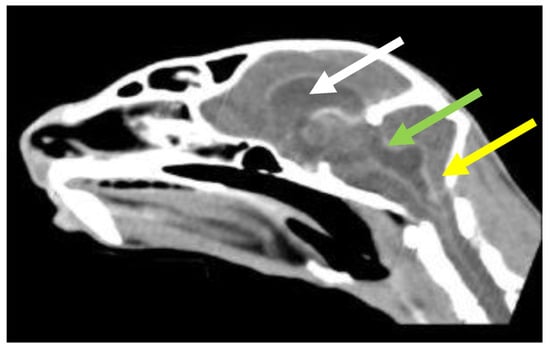

7.4. Diagnostic Imaging in FIP

7.4.1. Routine Imaging: Ultrasonographic and Radiographic Findings

7.4.2. Advanced Imaging of the CNS: MRI and CT

| Summary of Section 7: Diagnosis of FIP; Section 7.4: Diagnostic imaging in FIP: No specific ultrasonographic or radiographic findings exist for FIP. Ultrasonography (in particular) and radiography can show the presence of effusions. Pneumonia due to FIP that is occasionally reported can be associated with radiographic changes. Ultrasonography can reveal abdominal lymphadenomegaly or lymphadenopathy and/or abnormalities of the liver, spleen, intestines and/or kidneys (which can include a medullary rim sign), depending on which organs are affected. Imaging can also be of use to the direct sampling of abnormal tissues, e.g., fine-needle aspirate for cytology examination to reveal non-septic pyogranulomatous inflammation, or ultrasound-guided needle core (e.g., tru-cut) biopsies can be collected and submitted for histopathology. When a cat is showing neurological signs, the imaging of the brain by magnetic resonance imaging, if available, with contrast, can be useful to demonstrate neurological abnormalities (such as obstructive hydrocephalus, syringomyelia, foramen magnum herniation and marked contrast enhancement of the meninges, third ventricle, mesencephalic aqueduct, and brainstem). A description of computerised tomography findings in cats with neurological FIP has not been published, but MRI is likely to be more sensitive in the detection of subtle intraparenchymal lesions. Advanced imaging of the central nervous system is indicated before performing cerebrospinal fluid sampling to assess the potential risk of herniation. |